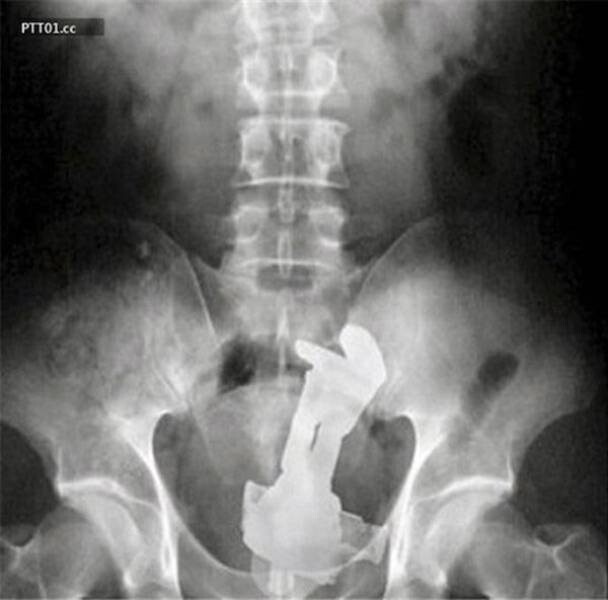

1. Ключи